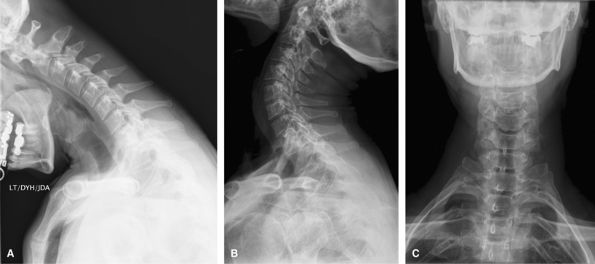

Flex-ext Series

The best way to assess for cervical stability. They

cannot be obtained acutely after trauma when there will likely be spasm

but should be delayed 10 days.

Figure 52 (A) Flexion lateral. (B) Extension lateral.